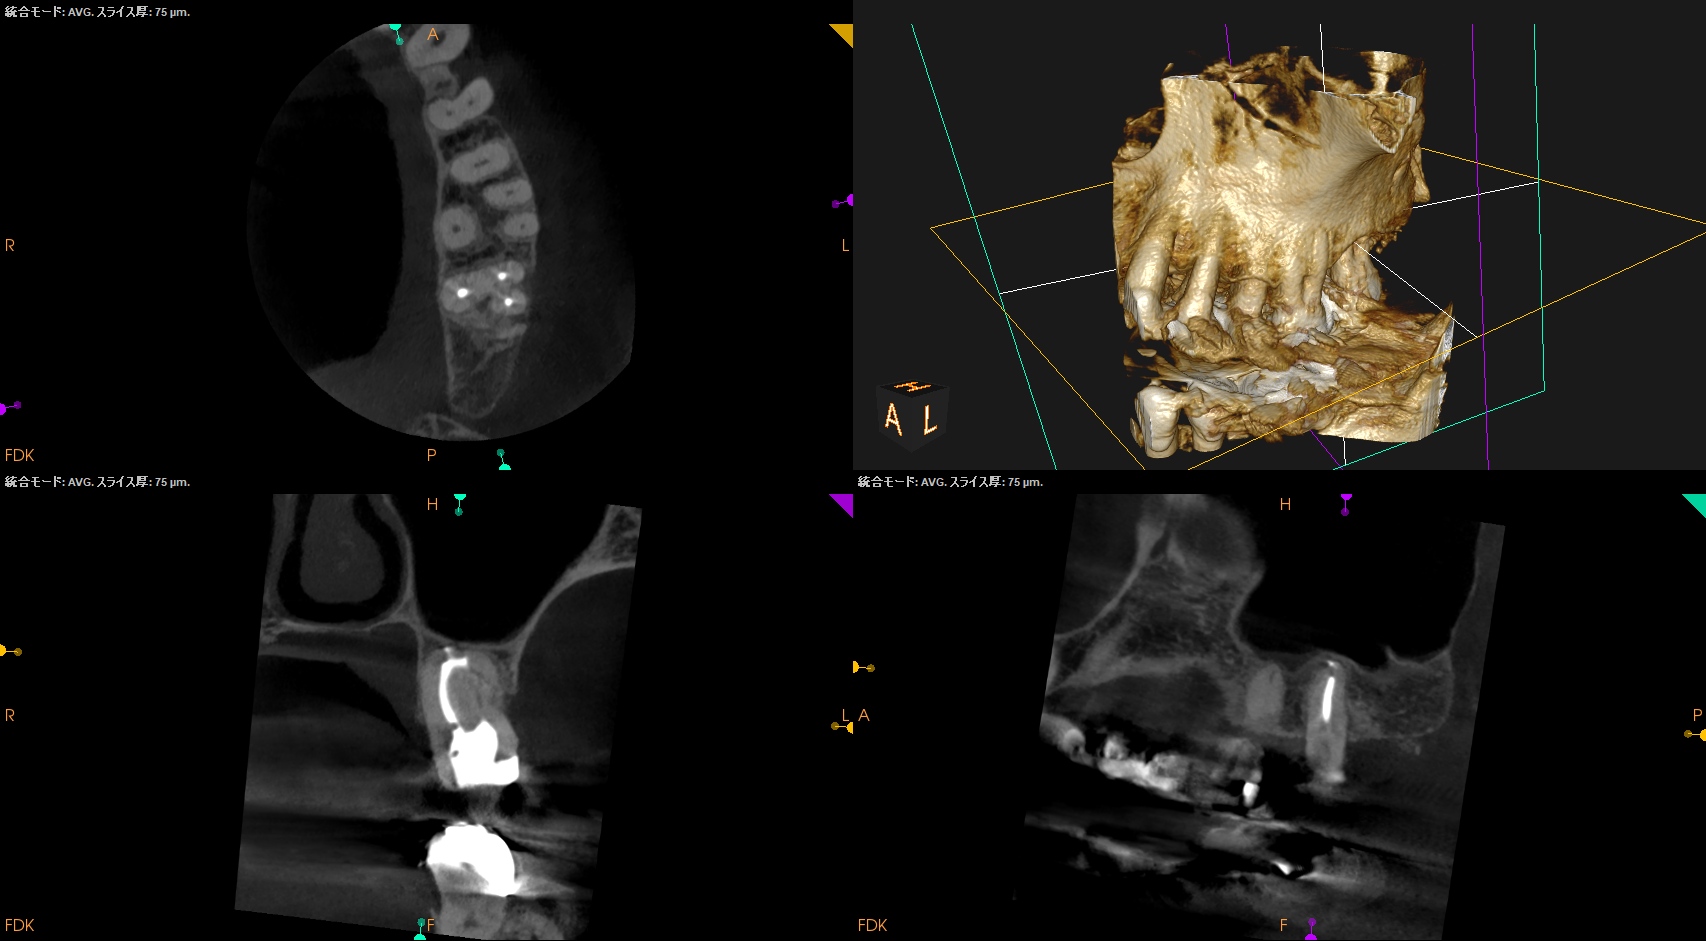

#15 RCT 1yr recall(2025.10.28)

MB

DB

P

初診時と比較した。

根尖病変、

術前の臨床症状、

術前の歯周ポケット

は完治した。

最終補綴もOKだ。

この日で経過観察も終診とさせていただいた。